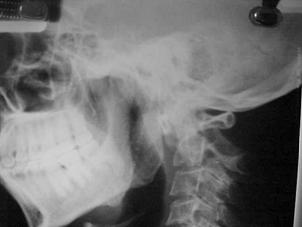

TRAUMA CERVICALA

Incidenta laterala Incidenta

laterala Incidenta

antero-posterioara